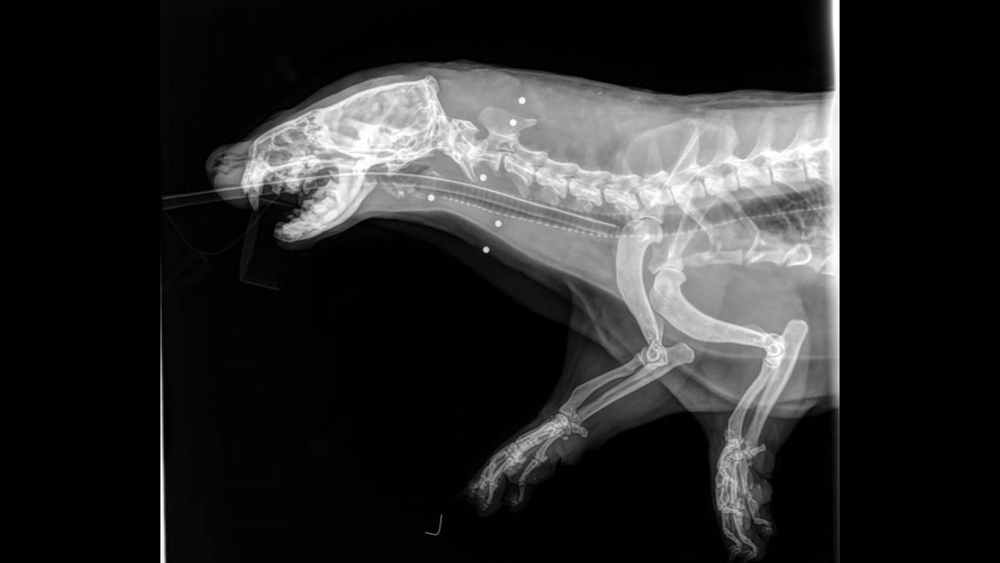

But that's apparently what happened to the male river otter found in Walnut Creek near the Shadelands Business park on Sunday. X-rays showed a half dozen bb's or possibly shotgun shot riddling its body. It was rushed to Lindsay Wildlife Hospital.

"He had broken teeth and something was going on in his mouth that wasn't right. His left eye was completely blind and in the wild, that's not a recipe for him to survive," said Lindsay Wildlife Hospital expert Elisabeth Nardi.